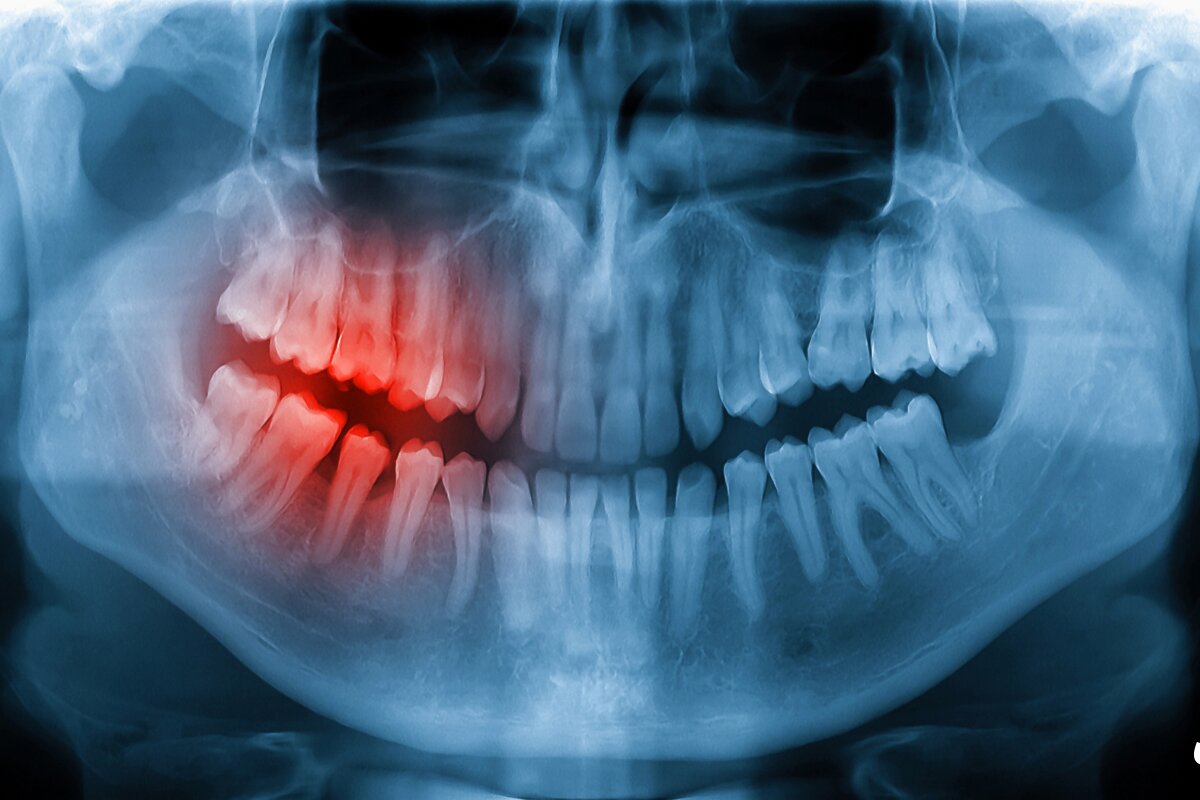

اورژانس دندانپزشکی مهر پارسه برای مدیریت مواردی چون درد شدید دندان، آبسه و تورم، شکستگی تاج و ریشه، خونریزی پس از جراحی، ضربه به دندانهای دائم و شیری، لقشدگی یا خارجشدن دندان (Avulsion)، شکستگی پروتز یا روکش، شکستن سیم و براکت ارتودنسی و حساسیتهای شدید پس از ترمیم آماده ارائه خدمات اورژانسی است. در بدو ورود، تریاژ با معیارهای استاندارد انجام میشود تا بیمارانی که خطر درگیری راه تنفس، تب بالا یا تورم شدید دارند در اولویت اقدام قرار گیرند.

پس از ثبت علائم، عکس رادیوگرافی دیجیتال (RVG) یا در صورت نیاز CBCT تهیه میشود. هدف نخست در اورژانس، تسکین درد و کنترل عفونت است؛ سپس تصمیم برای درمان قطعی یا موقت گرفته میشود. برای مثال، در ترکهای عمقی، باندینگ موقت و کنترل حساسیت انجام انجام خواهد شد و در ادامه درمان نهایی برنامهریزی میشود. در آبسهها، درناژ و آنتیبیوتیک با توجه به پروفایل بیمار تجویز میگردد و آموزش مراقبت خانگی و علائم هشدار بهصورت مکتوب تحویل داده میشود.